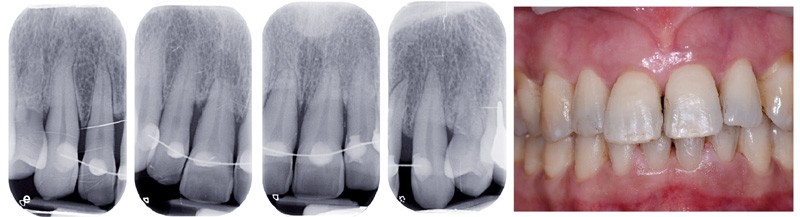

Bien souvent, dans les formes sévères, la diminution du boîtier osseux entraîne la migration et le déplacement de dents et notamment dans le secteur antérieur. Ces migrations ont un aspect disgracieux qui amène bon nombre de patients à consulter un orthodontiste pour corriger ces malpositions et retrouver à la fois une esthétique du sourire plus agréable et une fonction masticatrice plus efficace. Cependant, l’origine de ces migrations tient à l’inflammation du parodonte se traduisant par une plus grande laxité ligamentaire et une destruction du boîtier osseux. Dans certains cas, une surcharge occlusale aggrave encore le déplacement. Le traitement de l’inflammation par une thérapeutique initiale parodontale diminue la migration mais souvent, ne suffit pas à retrouver un positionnement correct (fig. 1). Il est alors nécessaire de mettre en œuvre une prise en charge orthodontique.